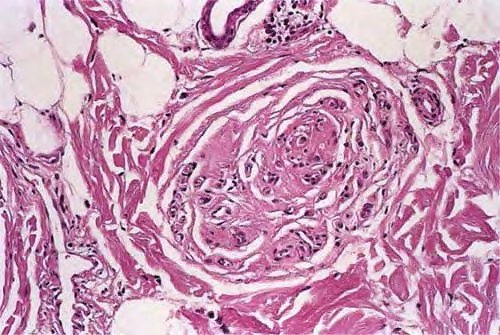

Diminution of follicular size, or miniaturization, is the histologic hallmark of AGA. To fully appreciate the number of miniaturized follicles, horizontal sections at the level of the lower infundibulum of terminal hair follicles should be examined because sections below this may miss the vellus hairs whose bulbs are situated in the upper dermis . Cursory inspection at low power reveals random variation in the caliber of hair follicles, consistent with a progressive miniaturization , and absence of well-defined follicular units . Although vellus hairs can be quickly identified by the fact that their shaft diameter is equal to or greater than the thickness of their inner root sheath, they are quantitatively defined as having a shaft diameter of 0.03 mm or less . In his 1984 paper that laid the groundwork for horizontal

interpretation of scalp biopsies, Headington also defined terminal hairs as having a shaft diameter of 0.06 mm or greater, thus recognizing an intermediate/indeterminate category in which the shaft diameter, i, measures 0.06 > > 0.03 mm, between terminal and vellus hairs . An optical micrometer may be used to measure hair shaft diameter, if necessary.

However, slightly different definitions were used in subsequent articles on AGA, specifically with regard to the intermediate category. For example, Whiting classified terminal hairs as having a “shaft diameter exceeding 0.03 mm … thicker than its inner root sheath,” thereby grouping intermediate hairs with the terminal hair population . He then used a 3:1 (or less) terminal-to-vellus hair ratio as being diagnostic of male pattern AGA, although at other times he and others quoted a terminal-to-vellus hair ratio of less than or equal to 2: 1 to diagnose AGA . Whiting found the average terminal-to-vellus ratio in AGA to be 1.7:1 . Using similar definitions of terminal and vellus hairs, Sperling and Winton reported finding an average terminal-to-vellus ratio of 1 :6.1 , illustrating how, in advanced cases, miniaturized hairs outnumber terminal hairs (. In my opinion, intermediate

hairs should be grouped with the vellus hair population because more often they represent a transitional follicle undergoing miniaturization to a vellus hair (unless the patient is using agents such as minoxidil or finasteride to reverse the process); unfortunately, ratios for normal scalp and in AGA in which vellus and intermediate hairs are lumped together are not available in the literature and remain to be determined.

The onset of AGA may be manifested by a telogen effluvium . Whiting found the telogen count in AGA to be 16.8%, as compared to 6.5% in controls (193), with telogen counts as high as 30% reported . Because the reduction in follicular size is associated with a shorter anagen phase (the smaller hairs do not grow as long), at a given point in time (for a histologic specimen this is the moment of biopsy harvest) a greater proportion of follicles will be found in telogen. There may be typical telogen hairs or, with increasing severity, telogen germinal units. A telogen germinal unit is the follicular epithelium that remains after the telogen hair shaft has been shed; it represents the secondary hair germ .Although vellus hairs continue to cycle through anagen and telogen in the papillary dermis, they are not considered to be part of the telogen count . Both miniaturization and increased conversion to telogen are associated with the finding of fewer terminal hair bulbs and more fibrous streamers in the deep dermis and subcutis . The fibrous streamers in AGA are thicker, more cellular, and possibly more fibrotic than those of normal follicles .

In advanced AGA there may be a reduced hair density with permanent loss of follicles, termed cicatricial pattern hair loss by Olsen and Olsen . Periinfundibular fibroplasia, ultimately leading to focal follicular scarring, may be responsible . In subtle cases, a second biopsy, taken from the occipital scalp, may be helpful for comparison because the occiput is typically uninvolved.